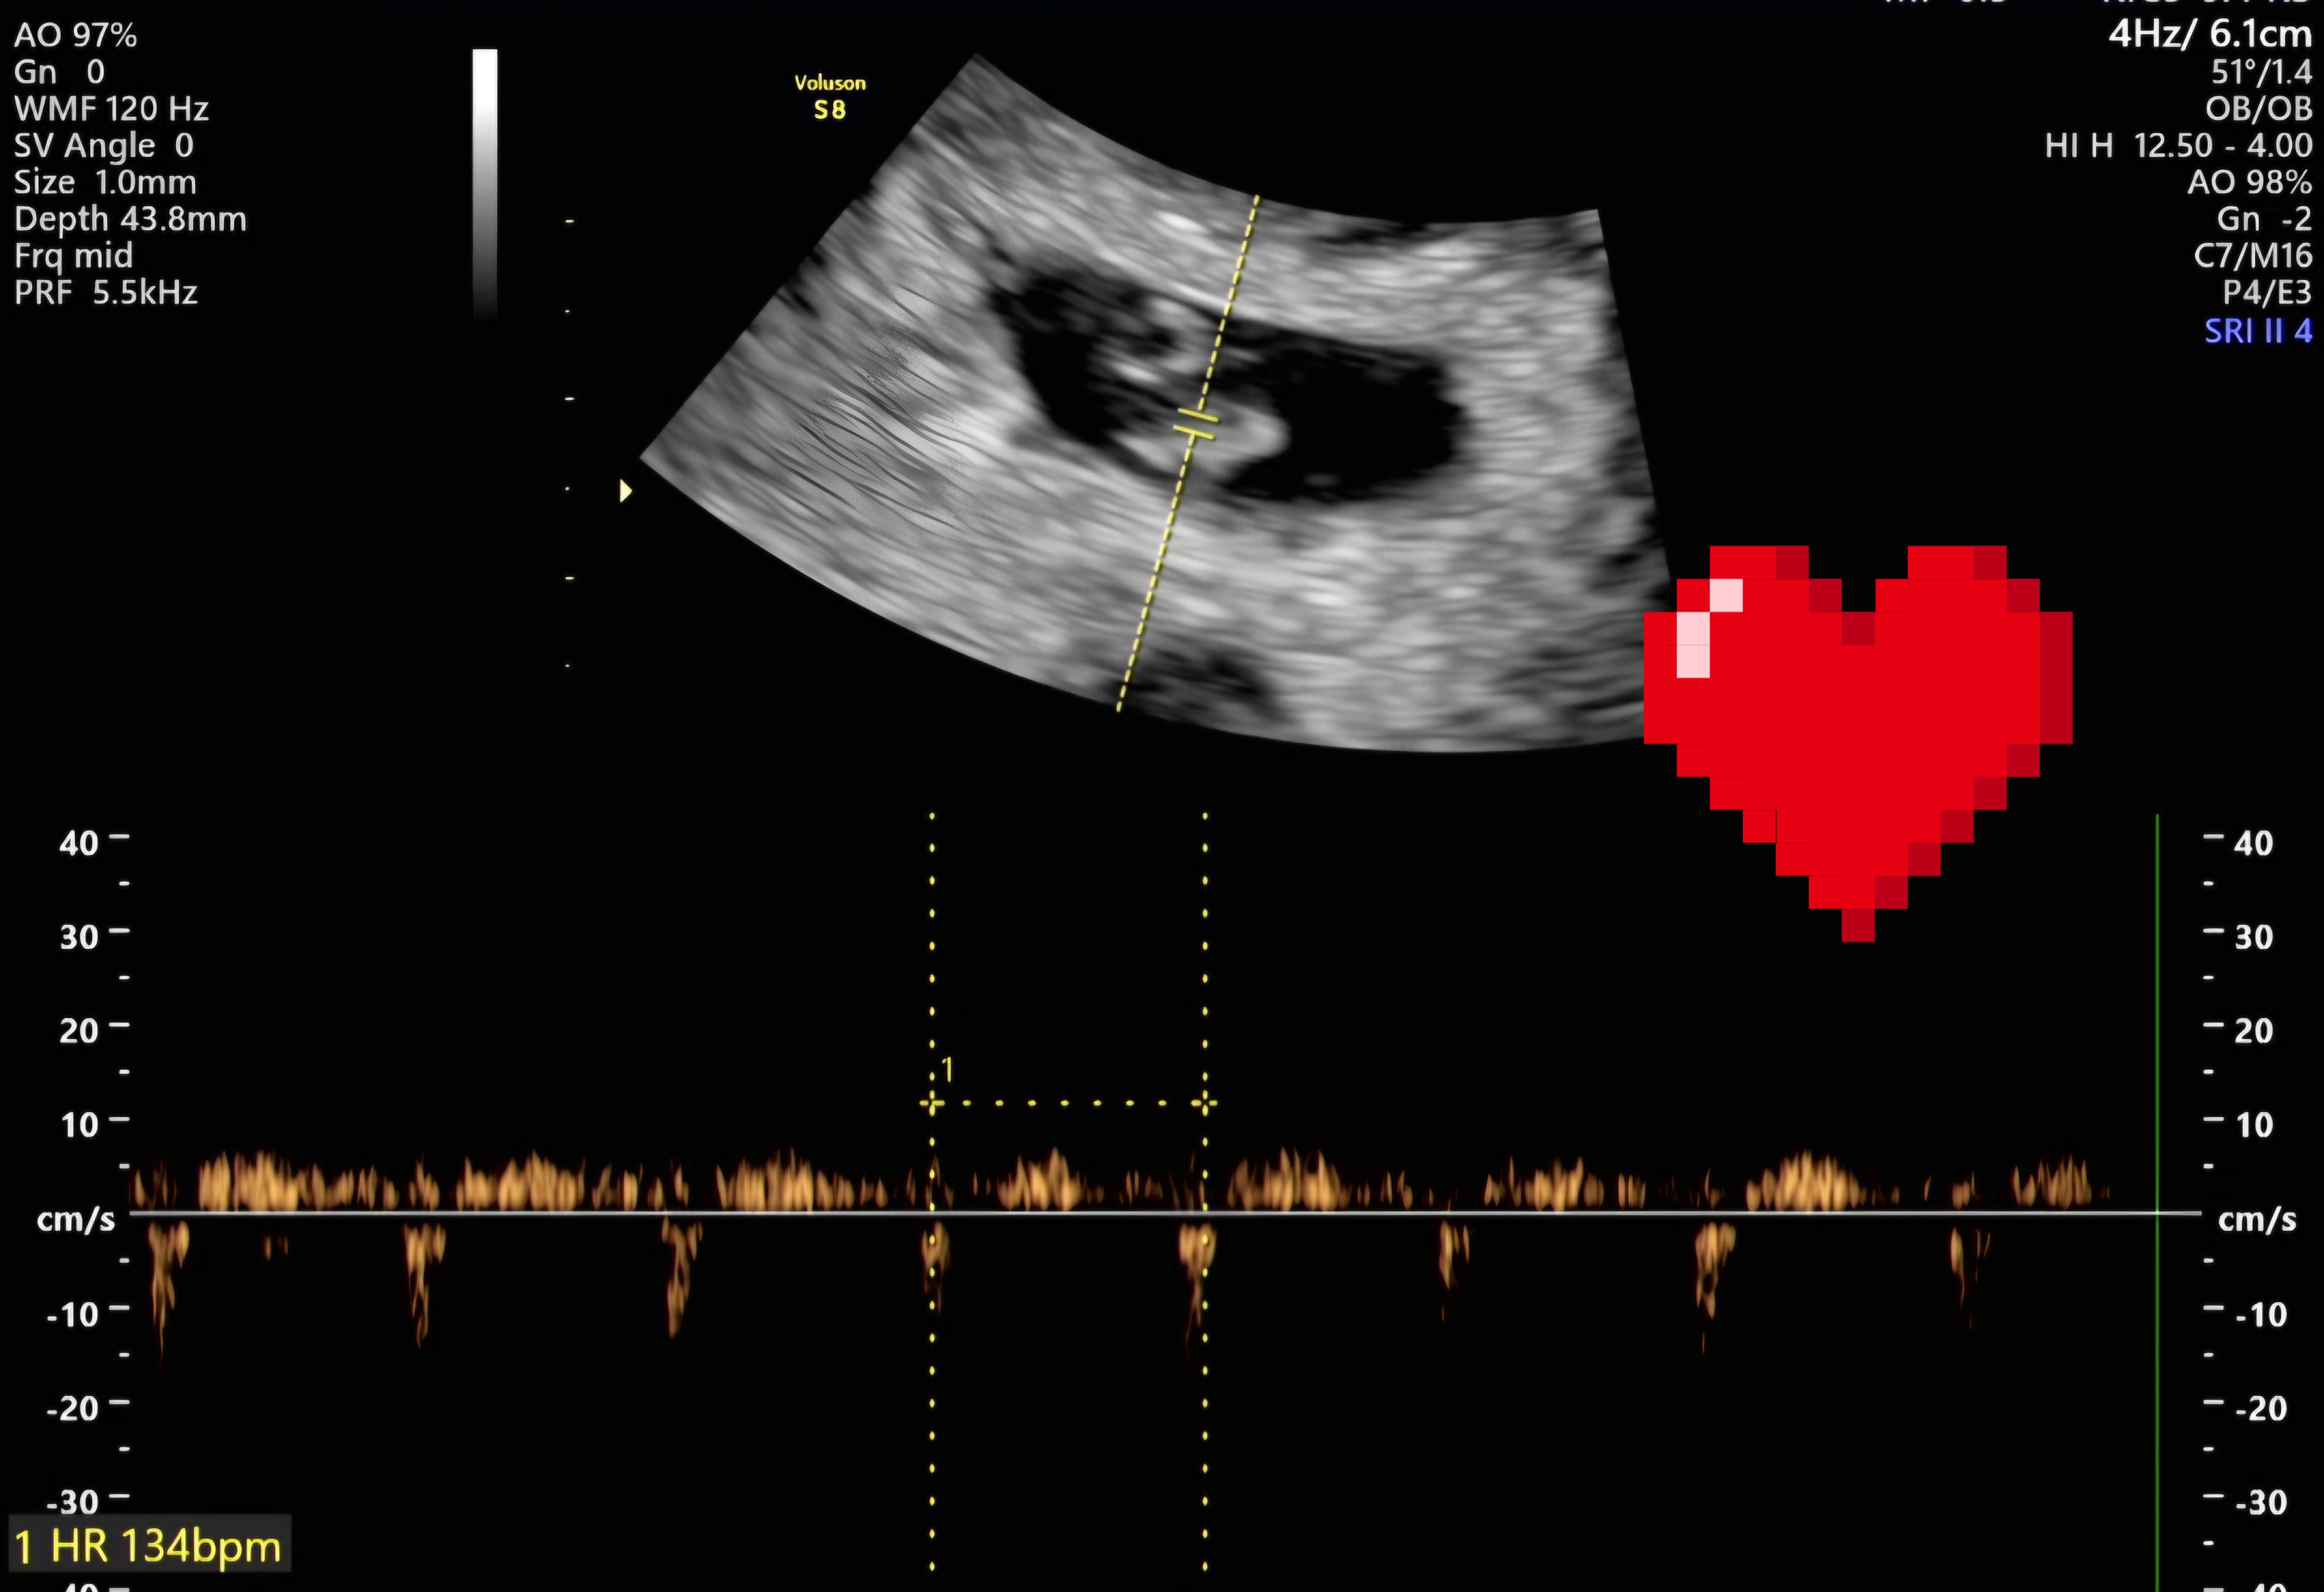

| 가슴 떨리는 임신 이야기를 공유해 주세요. | 저희 부부는 남성요인과 여성의 자궁내막증 수술 이력(한쪽 난소 일부만 남은 상태), 지속적인 재발, 그리고 40세에 가까운 나이라는 여러 조건 속에서 임신이 쉽지 않은 상황이었습니다. 혼인 후 6개월 자연임신을 시도한 뒤 바로 서울아이비에프여성의원을 찾아 검사를 받았고, 배란 유도 치료로 3회 자연임신 시도, 자궁경 폴립 제거, 인공수정 1회 후 시험관 시술을 진행하게 되었습니다. 난자 채취 이후 몸 상태 회복을 위해 원장님께서는 2개월 쉬고 오라고 하셨었는데 제가 느끼기에 괜찮다고 생각될 때를 기다리다보니 6개월정도를 충분히 휴식하고 내원하게 되었습니다. 그후 준비가 됐을 때 배아를 이식하고, 시험관 1차만에 아랫배를 콕콕 쑤시며 쪼꼬만 아기가 저희를 찾아와주었답니다. 기대가 크면 실망도 크니까, 1차 피검사 전날 잠은 한숨도 못 잤지만 임신테스트기는 안 하고 내원했거든요. 진료실에 들어가는 순간 이경훈 원장님께서 피검사수치를 보여주시면서, "축하드립니다 임신되셨네요~!" 하시는데, "어머! 정말요?" 하는 말이 저절로 나왔어요. 2차 피검사, 아기집 보는 날, 심장소리 듣는 날까지, 제 머릿속엔 생각을 많이 하지 않았어도 몸이 너무 긴장을 해서, 잠 한숨 못자고 심장 부여잡고 갔었네요. 가족들에게도 섣불리 말하지 못하고 끙끙 앓고 있던 불안한 마음이, 심장소리를 확인하는 순간 탁 풀려버리고, 안도의 미소가 지어졌어요. 남들은 심장소리 들을 때 눈물 흘린다던데, 저는 가족들에게 아기 소식을 알리면서 눈물파티 했네요 ; _ ; 40주의 여정 중 이제 7주차이지만, 무사히 출산까지 이어지길 기도하고 또 기도합니다 :) |